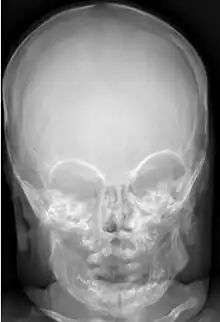

Many people with abnormally large heads or large skulls are healthy, but macrocephaly may be pathological. Pathologic macrocephaly may be due to megalencephaly (enlarged brain), hydrocephalus (abnormally increased cerebrospinal fluid), cranial hyperostosis (bone overgrowth), and other conditions. Pathologic macrocephaly is called "syndromic", when it is associated with any other noteworthy condition, and "nonsyndromic" otherwise. Pathologic macrocephaly may be caused by congenital anatomic abnormalities, genetic conditions, or by environmental events.[3]

Thick skull or scalp (hyperostosis)

Macrocephaly is customarily diagnosed if head circumference is greater than two standard deviations (SDs) above the mean.[11] Relative macrocephaly occurs if the measure is less than two SDs above the mean, but is disproportionately above that when ethnicity and stature are considered. Diagnosis can be determined in utero or can be determined within 18–24 months after birth in some cases where head circumference tends to stabilize in infants.[12] Diagnosis in infants includes measuring the circumference of the child's head and comparing how significant it falls above the 97.5 percentile of children similar to their demographic. If falling above the 97.5th percentile then the patient will be checked to determine whether there is any intracranial pressure present and whether or not immediate surgery is needed.[2] If immediate surgery is not needed then further testing will be done to determine whether the patient has either macrocephaly or benign macrocephaly.